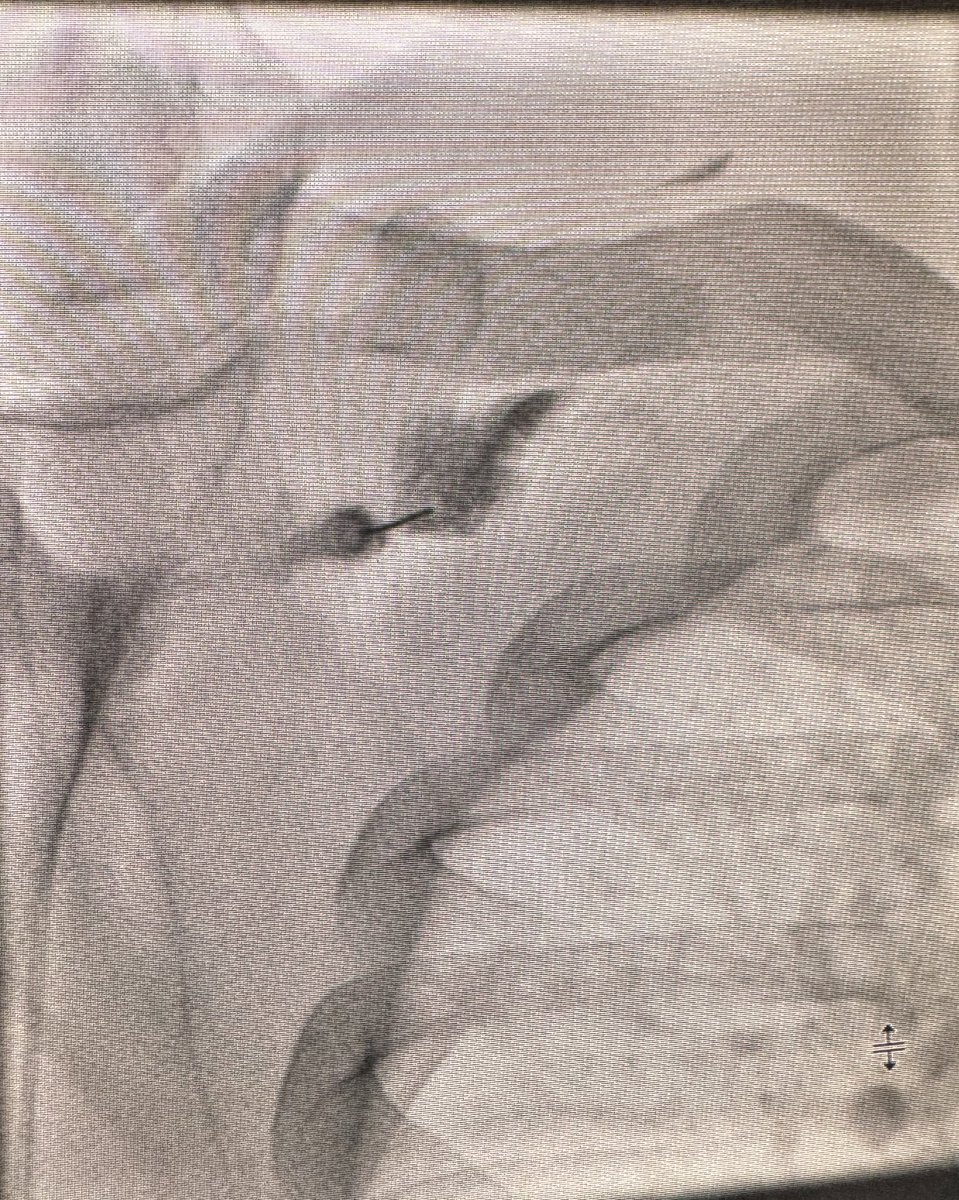

Beautiful flouroscopic suprascapular neurogram during a SSN block I did recently. I find these tricky with US and have had good results with FL. How are other people doing these? US or FL? Mass General Imaging Society of Skeletal Radiology